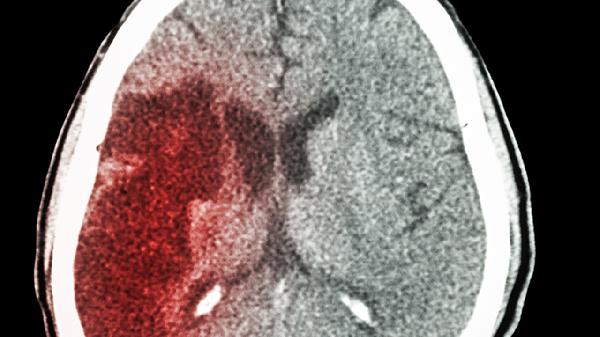

脑出血后偏瘫患者可在医生指导下使用依达拉奉注射液、胞磷胆碱钠片、阿司匹林肠溶片、盐酸乙哌立松片、多巴丝肼片等药物,以帮助改善神经功能、缓解肌张力障碍并预防并发症,促进恢复。

脑出血后偏瘫的恢复是一个综合过程,药物治疗需在神经内科或康复科医生指导下进行,切勿自行购药或更改方案。除用药外,系统的康复训练至关重要,包括物理治疗、作业治疗等,应尽早介入并长期坚持。饮食上需保证营养均衡,适当增加优质蛋白如鱼肉、蛋奶的摄入,多吃新鲜蔬菜水果以补充维生素和膳食纤维,控制盐分和脂肪摄入以管理血压血脂。家属应给予患者充分的心理支持,鼓励其参与康复,并注意预防跌倒、压疮、肺部感染等并发症。定期复查头颅CT或磁共振,监测病情变化,及时调整治疗策略。